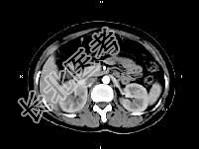

- 单项选择题女,27岁, 寒战高热、尿频、尿痛3天,尿检: 白细胞(+++),CT平扫及增强扫描如图所示, 下列说法错误的是 ( )

A、右肾体积增大

B、增强后右肾实质内可见条片状密度减低区

C、左肾未见异常

D、考虑为急性肾盂肾炎

E、考虑为慢性肾盂肾炎